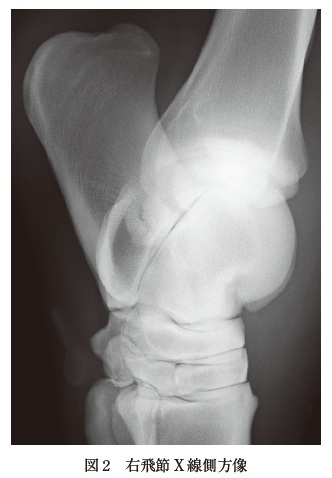

来院時検査所見:視診では右後肢の跛行(Grade3)があり,右飛節以下がやや腫脹していた.触診では腫脹部位の圧痛はあまりなく,飛節の熱感,屈曲痛,及び関節液の軽度増量がみられた.体温は38.1℃,安静時心拍数は52 回/ 分,安静時呼吸数は28 回/ 分であった.また,聴診では拡張期心雑音(Levine 分類3/6)が聴取された.身体検査ではその他に異常所見は認められなかった.臨床検査として,血液生化学検査(表),血清蛋白電気泳動検査(図1),飛節のX 線検査(図2),心エコー検査(図3,B モード及びカラードプラー)を行った.

微熱,頻脈,頻呼吸,拡張期心雑音(Levine 分類3/6)の聴取,白血球数の著しい増加,TPの高値,A/G 比の低下,グロブリン分画の増加,SAA の軽度高値,心エコー検査B モードでは大動脈弁の疣贅形成,さらにカラードプラーでは大動脈弁左心室方向への逆流がみられたことにより,大動脈閉鎖不全を伴う感染性心内膜炎に罹患していると考えられる.また飛節X 線像では踵骨載距突起部線状透亮像を認めるが,外力による骨折の可能性は否定できないものの,その形状がシャープではなく,そもそも当該部位は骨折の好発部位ではないことから骨折と診断しない.仮に骨折であれば,受傷時にGrade4以上の重度跛行を示すことが一般的であるが,本症例は重度跛行を示すことがなかった.したがって,本症例における右後肢の跛行及び関連した所見は,外傷や骨折によるものというより,感染性心内膜炎により引き起こされた転移性感染,免疫複合体沈着または塞栓に起因した関節炎の可能性が高いと考えられる.

本症例の主訴である右後肢の跛行について,身体検査にて右飛節に異常所見がみられたため,飛節のエコー検査及びX 線検査を行った.エコー検査では飛節関節液のわずかな増量がみられたのみであった.X 線検査では,踵骨載距突起部に線状の透亮像がみられたが,その他に異常所見はみられなかった.本症例の跛行には重度感染症が関連していることが推察されたため,この線状の透亮像は,外力が加わることによって生じた骨折というよりむしろ,感染性心内膜炎に関連している可能性が高いことが考えられた.馬の感染性心内膜炎の症状は多岐にわたることが知られている.通常,断続的な発熱,体重減少,元気消失,食欲不振等がみられるが,しばしば跛行や関節液の増量がみられることがある.感染性心内膜炎による跛行の原因としては,転移性感染,免疫複合体沈着及び塞栓が関連していると考えられている.